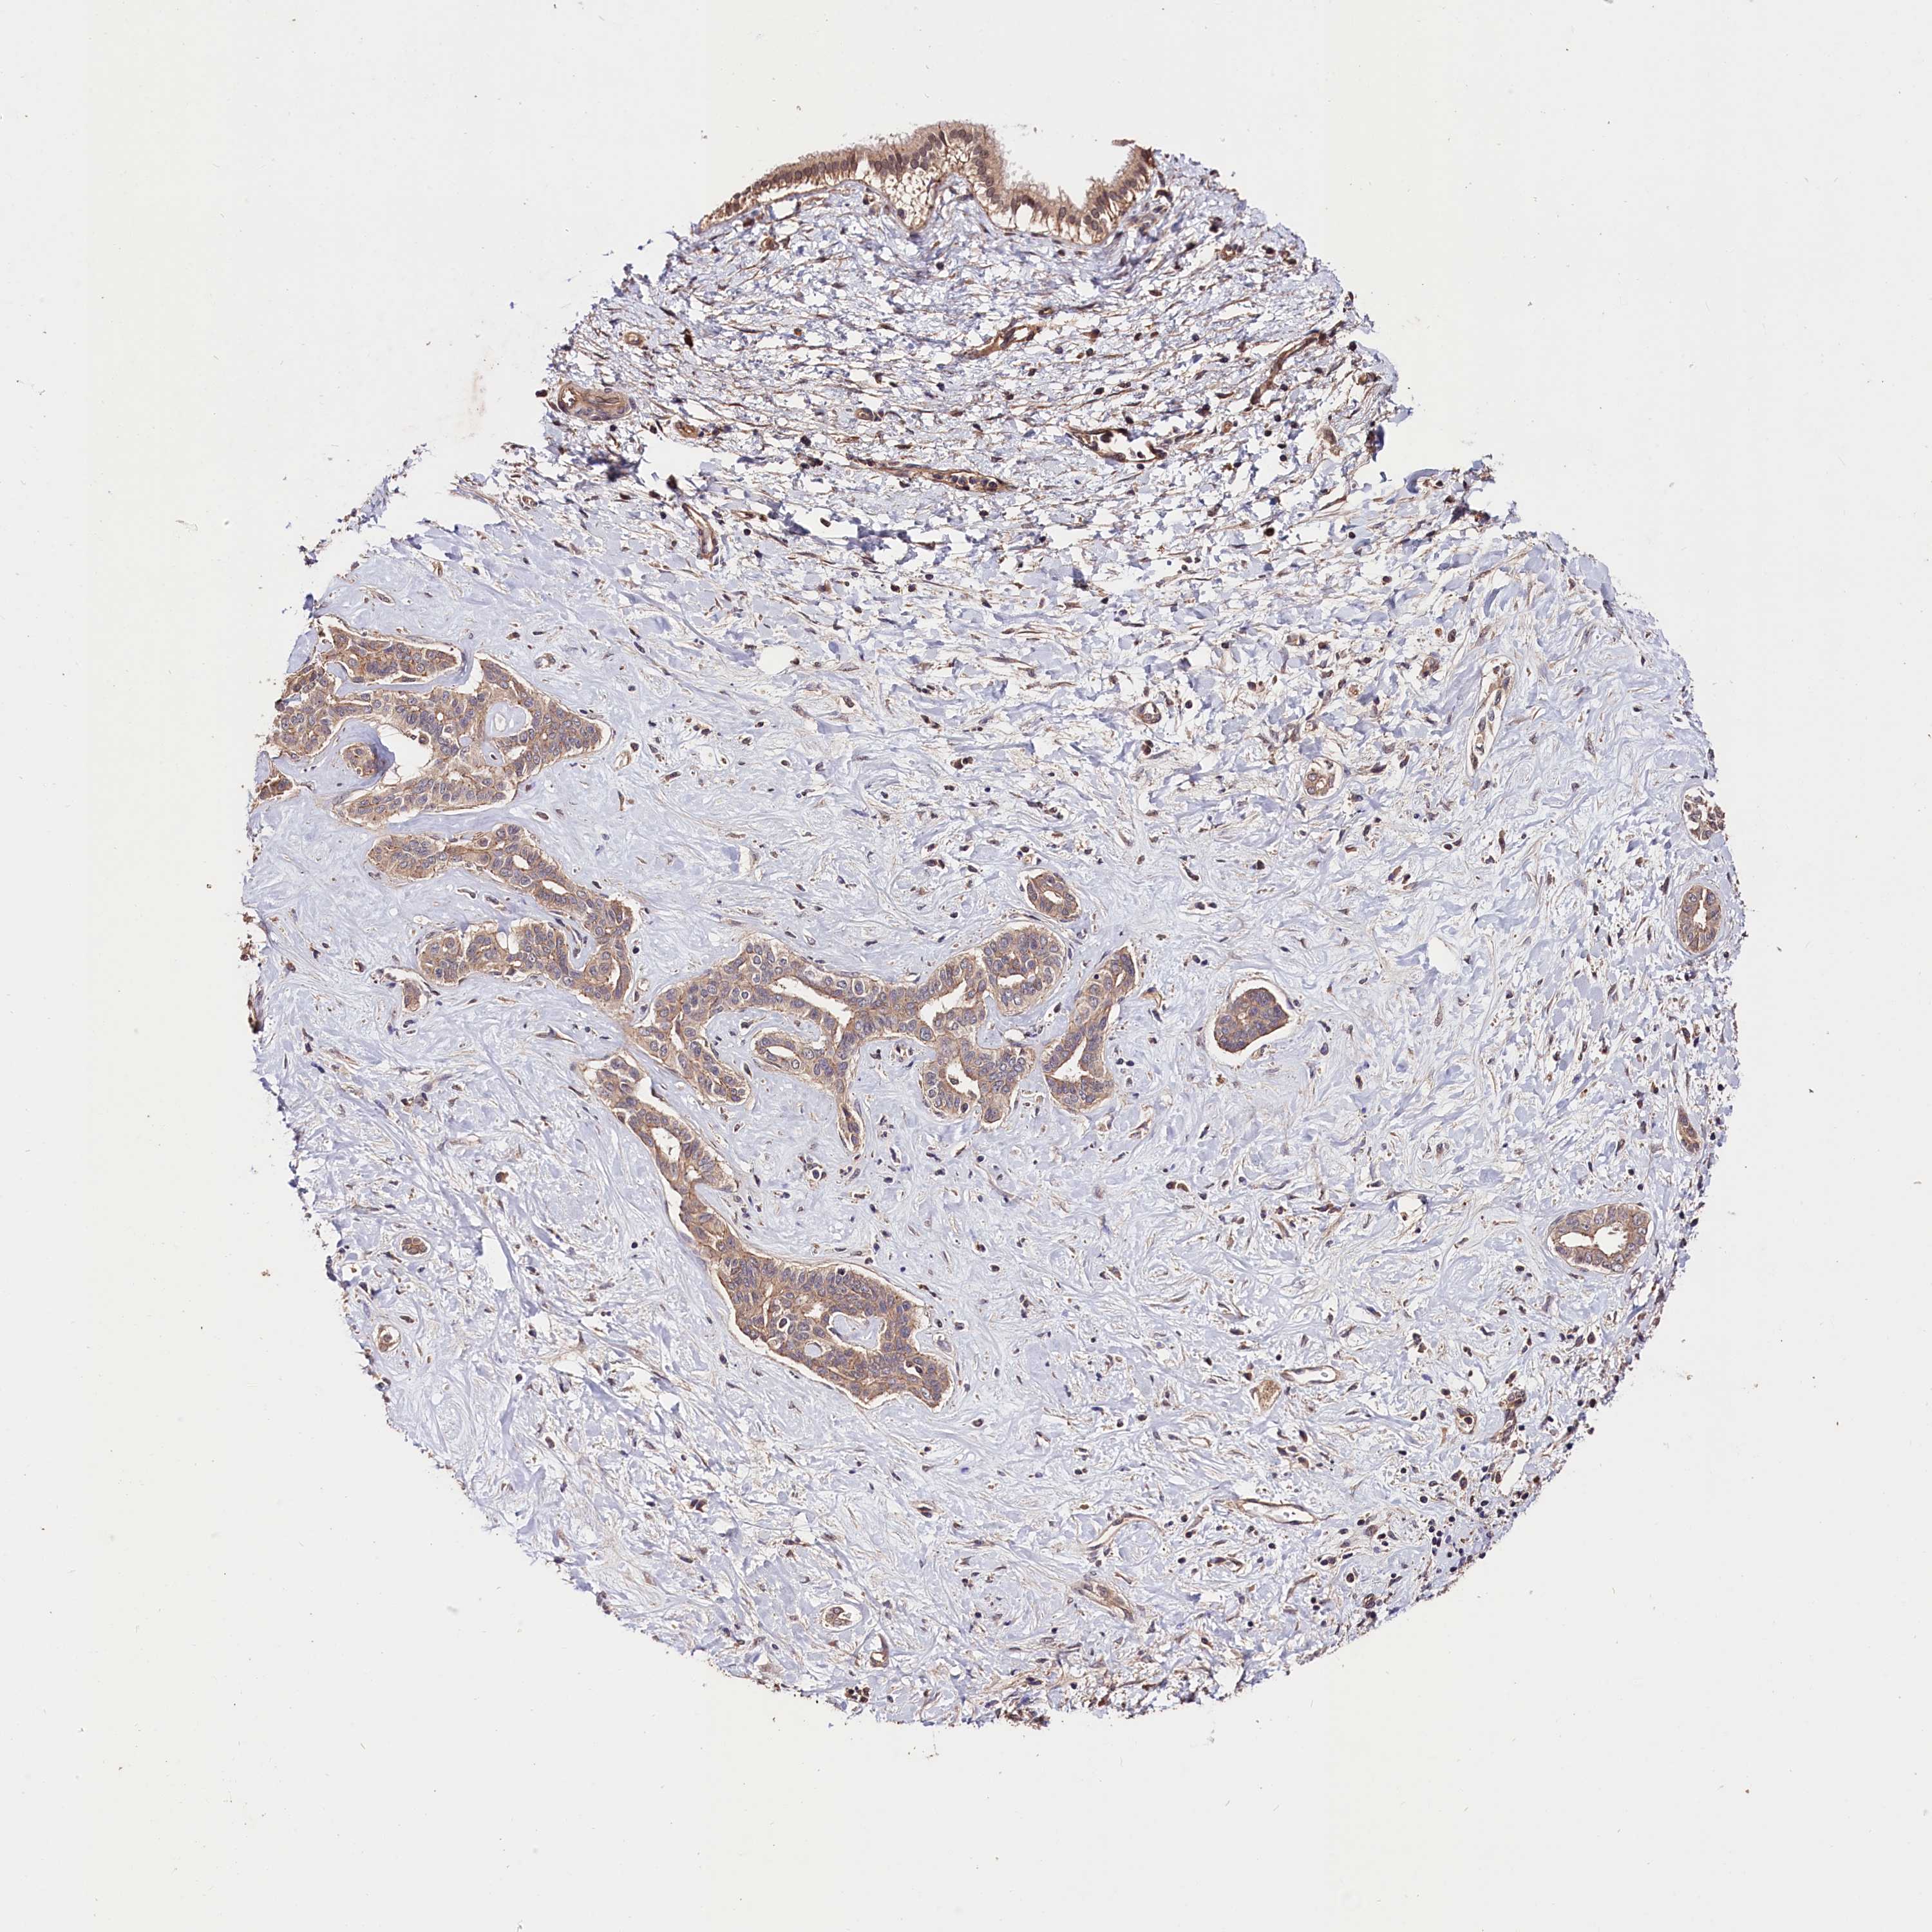

LIVER CANCER - Protein expressioni

A mouse-over function shows sample information and annotation data. Click on an image to view it in a full screen mode. Samples can be filtered based on level of antibody staining by selecting one or several of the following categories: high, medium, low and not detected. The assay and annotation is described here.

Note that samples used for immunohistochemistry by the Human Protein Atlas do not correspond to samples in the TCGA dataset.

Antibody stainingi

Antibody staining in the annotated cell types in the current human tissue is reported as not detected, low, medium, or high, based on conventional immunohistochemistry profiling in selected tissues. This score is based on the combination of the staining intensity and fraction of stained cells.

Each image is clickable and will lead to virtual microscopy that enables deeper exploration of all samples and also displays staining intensity scores, fraction scores and subcellular localization as well as patient and tissue information for each sample.

Antibody HPA041008

Antibody HPA041307

Staining

High

Medium

Low

Not detected

Intensity

Strong

Moderate

Weak

Negative

Quantity

>75%

75%-25%

<25%

None

Location

Nuclear

Cytoplasmic/membranous

Cytoplasmic/membranous,nuclear

Cholangiocarcinoma

Carcinoma, Hepatocellular, NOS